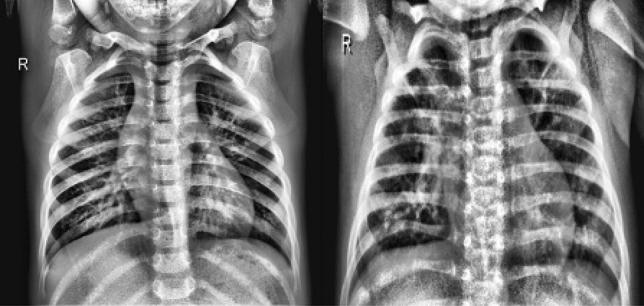

Pneumonia, an acute respiratory infection, causes serious breathing hindrance by damaging lung/s. Recovery of pneumonia patients depends on the early diagnosis of the disease and proper treatment. This paper proposes an ensemble method-based pneumonia diagnosis from Chest X-ray images. The deep Convolutional Neural Networks (CNNs)-CheXNet and VGG-19 are trained and used to extract features from given X-ray images. These features are then ensembled for classification. To overcome data irregularity problem, Random Under Sampler (RUS), Random Over Sampler (ROS) and Synthetic Minority Oversampling Technique (SMOTE) are applied on the ensembled feature vector. The ensembled feature vector is then classified using several Machine Learning (ML) classification techniques (Random Forest, Adaptive Boosting, K-Nearest Neighbors). Among these methods, Random Forest got better performance metrics than others on the available standard dataset. Comparison with existing methods shows that the proposed method attains improved classification accuracy, AUC values and outperforms all other models providing 98.93% accurate prediction. The model also exhibits potential generalization capacity when tested on different dataset. Outcomes of this study can be great to use for pneumonia diagnosis from chest X-ray images.

肺炎是一种急性呼吸道感染,通过损害肺部导致严重的呼吸障碍。肺炎患者的康复取决于疾病的早期诊断和适当治疗。本文提出了一种基于集成方法的胸部X光图像肺炎诊断方法。对深度卷积神经网络(CNN)——CheXNet和VGG - 19进行训练,并用于从给定的X光图像中提取特征。然后将这些特征进行集成以进行分类。为了克服数据不均衡问题,对集成特征向量应用随机欠采样(RUS)、随机过采样(ROS)和合成少数类过采样技术(SMOTE)。然后使用几种机器学习(ML)分类技术(随机森林、自适应提升、K近邻)对集成特征向量进行分类。在这些方法中,随机森林在可用的标准数据集上比其他方法获得了更好的性能指标。与现有方法的比较表明,所提出的方法提高了分类准确率、AUC值,并且优于所有其他模型,提供了98.93%的准确预测。该模型在不同数据集上进行测试时也表现出潜在的泛化能力。本研究的结果对于利用胸部X光图像进行肺炎诊断可能非常有用。